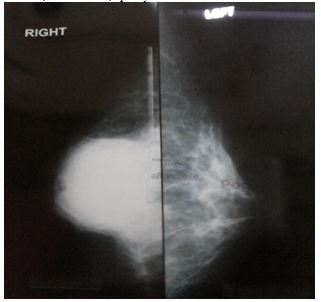

Kumar et al. [12] reported a 31-year-old lady who had presented with a gradually progressive, painless lump within her right breast over a period of one year. She did not have any past medical history of injury, discharge from her nipple, or a family history of carcinoma of the breast. She was a housewife who did not disclose having had any close contact with any animal. She was found upon examination to have a non-mobile, firm lump that measured 5 cm x 5 cm within the sub-areolar region of her right breast which was predominantly located within the upper quadrants of the breast. The nipple of her right breast was noted to be retracted. The left breast and nipple were found on examination to be normal and there was no evidence of axillary or cervical lymph adenopathy. She had mammogram which showed a large, smooth walled, well-defined, opacity in the right sub-areolar region (see figure 7). The left breast was normal. She had ultrasound scan of her breasts which showed a thick walled cystic lesion with floating membranes as well as internal echoes within the sub-areolar region of her right breast. She also had chest x-ray and ultrasound scan of her abdomen and which were normal. She underwent excision of the right breast lump in which the right breast lump was removed completely via a curvilinear incision just above the areolar margin (see figures 8 and 9). The excised cyst was found on gross examination to be oval in shape and it had measured 5 cm x 4.5 cm x 3 cm. upon opening of the cyst, endocysts were visualised which did confirm that the cyst was a hydatid cyst (see figure 10).